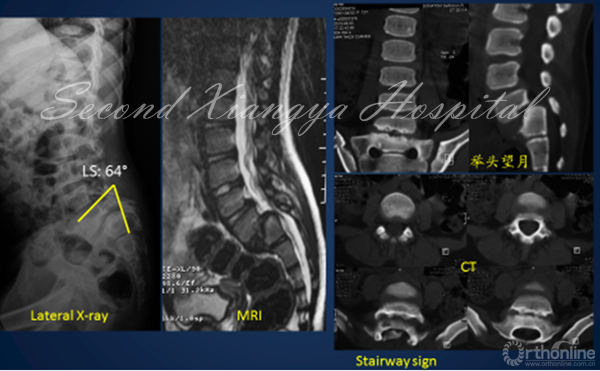

1. 骶骨形态重度不良

对重度骶骨发育不良者,先天遗传是主要原因。2015年,罗卓荆团队通过两个家系[6],鉴定了2个新型错义突变,功能研究显示软骨发育过程中,磷酸化摄入障碍是其发病主要的分子机制。遗传因素造成的骶骨穹窿形态不良,通常较为严重,并会造成L5椎体梯形变,导致滑脱进展,并使得外科治疗此类畸形较为困难。

2. 骶骨形态不规则

骶骨形态不规则,通常是由于力学因素造成的。2012年,Sevrain[7]根据PI值将滑脱分为低PI组和高PI组,生物力学测试结果表明,低PI组人体重心位于骶骨中后区,而高PI组重心则分布在骶骨前方。从而更容易造成骶骨形态发生轻度或中度形态变化,L5椎体出现相应梯形变,从而亦会造成滑脱进展。

① 对于失平衡不重者,可以采取一期后路部分复位和经骶骨轴向融合方式[4]。

② 明显失平衡者,采取后路复位联合前路支撑重建术式。

① 采取前后联合,骶骨部分截骨、复位和椎间支撑重建手术[8]。